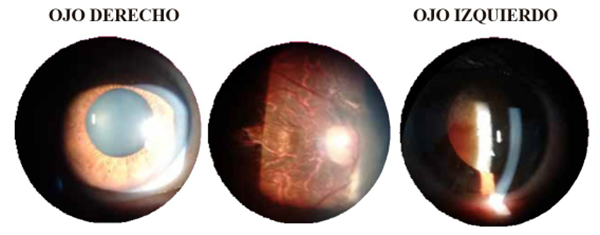

Caso 3

J.C.C. Masculino de 34 años de edad. MC: Concurre a la consulta a fin de completar formulario de discapacidad.

En este caso, a diferencia de los dos precedentes se trata de lesiones autoinflingidas en una tentativa de suicidio ocurrida a la edad de 22 años. Refiere que al encontrarse en estado de desesperación por no poder abandonar el consumo de estupefacientes decide quitarse la vida.

Apoyó su arma en la sien derecha y abrió fuego. El proyectil a travesó ambas órbitas seccionando los nervios ópticos, pero quedando vivo. Refiere que el proyectil quedó alojado en la órbita izquierda. Se solicitaron imágenes pero nunca volvió a la consulta. Por el orificio de entrada (ver fotografía de perfil) y la magnitud de las lesiones se deduce que se trató de un proyectil de bajo calibre (lo más probable 22 centésimas de pulgada).

Se lo examinó el día 5 de julio de 2019

• AV c/cv AO No luz

• Pupilas en midriasis media OD y midriática OI.

• Arreactivas a la luz (ver fotos de pupilas).

• BMC: OD Medios refringentes transparentes. CA formada, libre y de profundidad uniforme. Iris trófico y en midriasis media. OI Córnea transparente, CA formada, libre y de profundidad uniforme. Cristalino: Catarata rubra (ver fotografía).

• Po  OD 16 mmHg - OI 15 mmHg.

• Fondo de ojo: OD se observa área de movilización pigmentaria en el polo posterior y velo fibrótico nasal a la papila que se observa. Papila atrófica (Figuras 8 y 9).

• OI de práctica imposible por opacidad de los medios.

Figura 8

Figura 9: ojo derecho y ojo izquierdo.